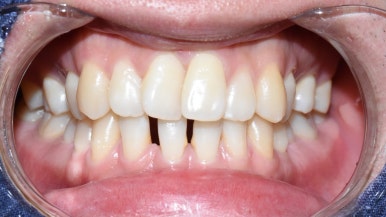

거두절미하고, 백문이 불여일견이니

앞니레진. 저희 치과에서 진행한 앞니 레진치료 사진

전후사진 여러 케이스들을 공개합니다.

[환자분들의 동의를 얻은 사진만 게시합니다.]

다이아스테마(앞니 사이 벌어진 부분) 레진 치료

다이아스테마 레진치료